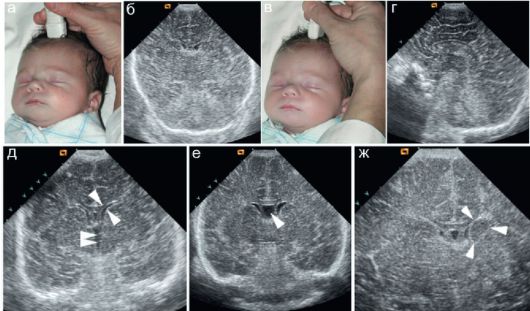

Провідним способом обстеження при псевдокисте вважається ультразвук. Однак він не дозволяє уважно оглянути стінки і внутрішній простір порожнини. Орієнтуються на конкретні ділянки, де зазвичай формується псевдокиста головного мозку у новонароджених.

Увагу звертають на великі півкулі мозку, бічні шлуночки, зону розташування голівки хвостатого ядра зорового бугра. Особливості локалізації дають можливість розрізнити псевдокисту, не сплутати її з істинною кістою.

На наявність освіти вказують ехоознаки субэпендимальной псевдокисты області лівого або правого шлуночка. Застосування ультразвукових хвиль ефективно тільки поки малюкові не виповнився рік, так як його джерельце ще не закритий кістками. Показаннями для обстеження є:

У комплексі з ультразвуком використовують такі методи:

- доплеровскую энцефалографию;

- нейросонографію;

- комп’ютерну та магнітно-резонансну томографію;

- церебральну сцинтиграфію;

- позитронно-емісійну томографію.